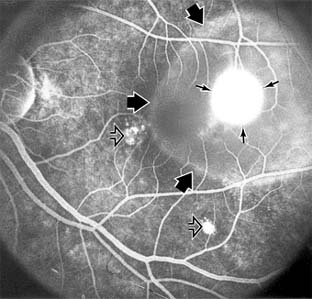

MACULAR EDEMA

Retinal edema involving the macula may be associated with a variety of intraocular inflammatory diseases, retinal vascular diseases, intraocular surgery, inherited or acquired retinal degenerations, medications, macular membranes, or unknown causes. Macular edema may be diffuse, with nonlocalized intraretinal fluid causing thickening of the macula. When edema fluid accumulates in honeycomb-like spaces of the outer plexiform and inner nuclear layers, it is called cystoid macular edema. On fluorescein angiography, fluorescein dye leaks from the perifoveal retinal capillaries and accumulates in a flower-petal pattern about the fovea (Figure 10-4).

Figure 10-4

Figure 10-4: Flower-petal pattern of fluorescein dye in a patient with cystoid macular edema after cataract surgery.

The most widely recognized association with cystoid macular edema is intraocular surgery. Approximately 50% of eyes undergoing uneventful intracapsular cataract extraction and 20% of eyes undergoing extracapsular cataract extraction develop angiographic cystoid macular edema. Clinically significant edema usually occurs within 4-12 weeks postoperatively, but in some instances its onset may be delayed for months or years. Many patients with cystoid macular edema of less than 6 months' duration have self-limited leakage that will resolve without treatment. Topical or local (or both) anti-inflammatory therapy may be of value in restoring visual acuity in some patients with chronic postoperative macular edema. YAG laser vitreolysis (see Chapter 24) and surgical vitrectomy may be of benefit when the macular edema is associated with vitreous tissue incarcerated in the cataract wound or adherent to anterior segment structures. When an intraocular lens implant is the cause of postoperative macular edema due to its design, positioning, or inadequate fixation, removal of the lens implant can be considered.